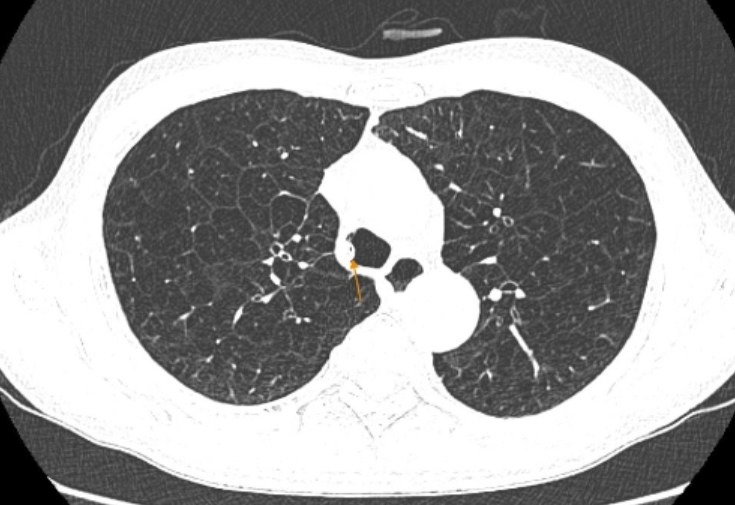

Kết quả chụp CT phổi ghi nhận hình ảnh viêm phế quản mạn tính, giãn phế nang lan tỏa hai phổi là những tổn thương điển hình của COPD, kèm ứ đọng dịch nhầy trong lòng khí quản.